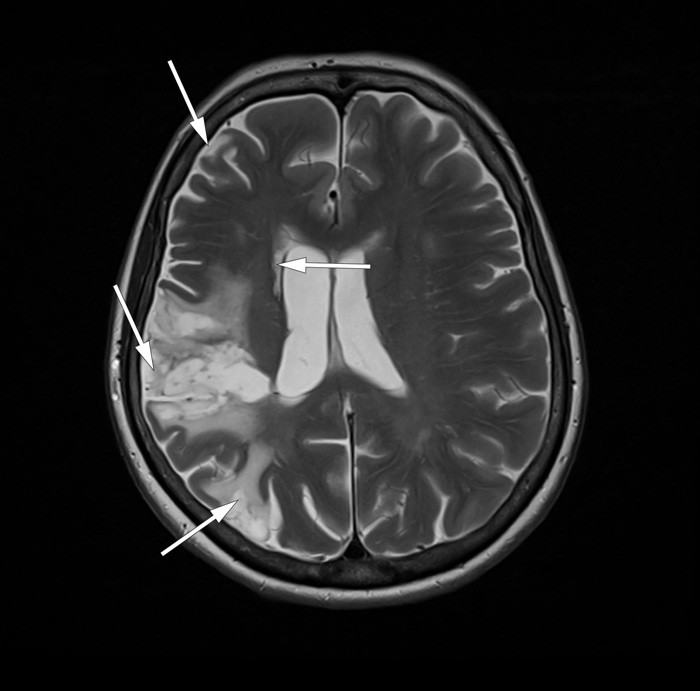

En ellers frisk kvinne i 50-årene fikk akutt hjerneinfarkt i høyre cerebrale hemisfære ti år etter gjennomgått nakkekirurgi med fiksasjon av virvlene C4-C7 via fremre tilgang.

De to første årene etter dette akutte hjerneinfarktet hadde hun multiple transitoriske iskemiske anfall (TIA) og flere MR-bekreftede spredte infarkter i høyre hemisfære (bilde kun i nettutgaven), til tross for platehemmende og antikoagulerende behandling. Hun utviklet dysartri, venstre facialisparese og venstresidige sensimotoriske utfall. Grundig utredning inkludert ultralyd precerebrale halskar og CT-angiografi avdekket i denne perioden ikke embolikilde.